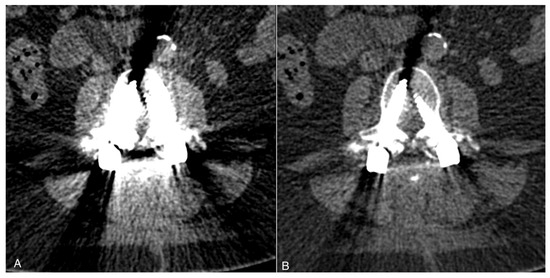

Immunohistochemistry Reveals TRPC Channels in the Human Hearing Organ—A Novel CT-Guided Approach to the Cochlea

TRPC channels are critical players in cochlear hair cells and sensory neurons, as demonstrated in animal experiments. However, evidence for TRPC expression in the human cochlea is still lacking. This reflects the logistic and practical difficulties in obtaining human cochleae. The purpose of [...] Read more.

TRPC channels are critical players in cochlear hair cells and sensory neurons, as demonstrated in animal experiments. However, evidence for TRPC expression in the human cochlea is still lacking. This reflects the logistic and practical difficulties in obtaining human cochleae. The purpose of this study was to detect TRPC6, TRPC5 and TRPC3 in the human cochlea. Temporal bone pairs were excised from ten body donors, and the inner ear was first assessed based on computed tomography scans. Decalcification was then performed using 20% EDTA solutions. Immunohistochemistry with knockout-tested antibodies followed. The organ of Corti, the stria vascularis, the spiral lamina, spiral ganglion neurons and cochlear nerves were specifically stained. This unique report of TRPC channels in the human cochlea supports the hypothesis of the potentially critical role of TRPC channels in human cochlear health and disease which has been suggested in previous rodent experiments. Full article